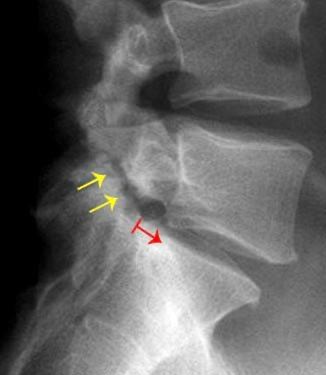

Q126. What is the most appropriate diagnosis for the image below?

- Spondylolisthesis

- Spondylolysis

- Vertebral compression fracture

- Degenerative disc disease

Answer: A